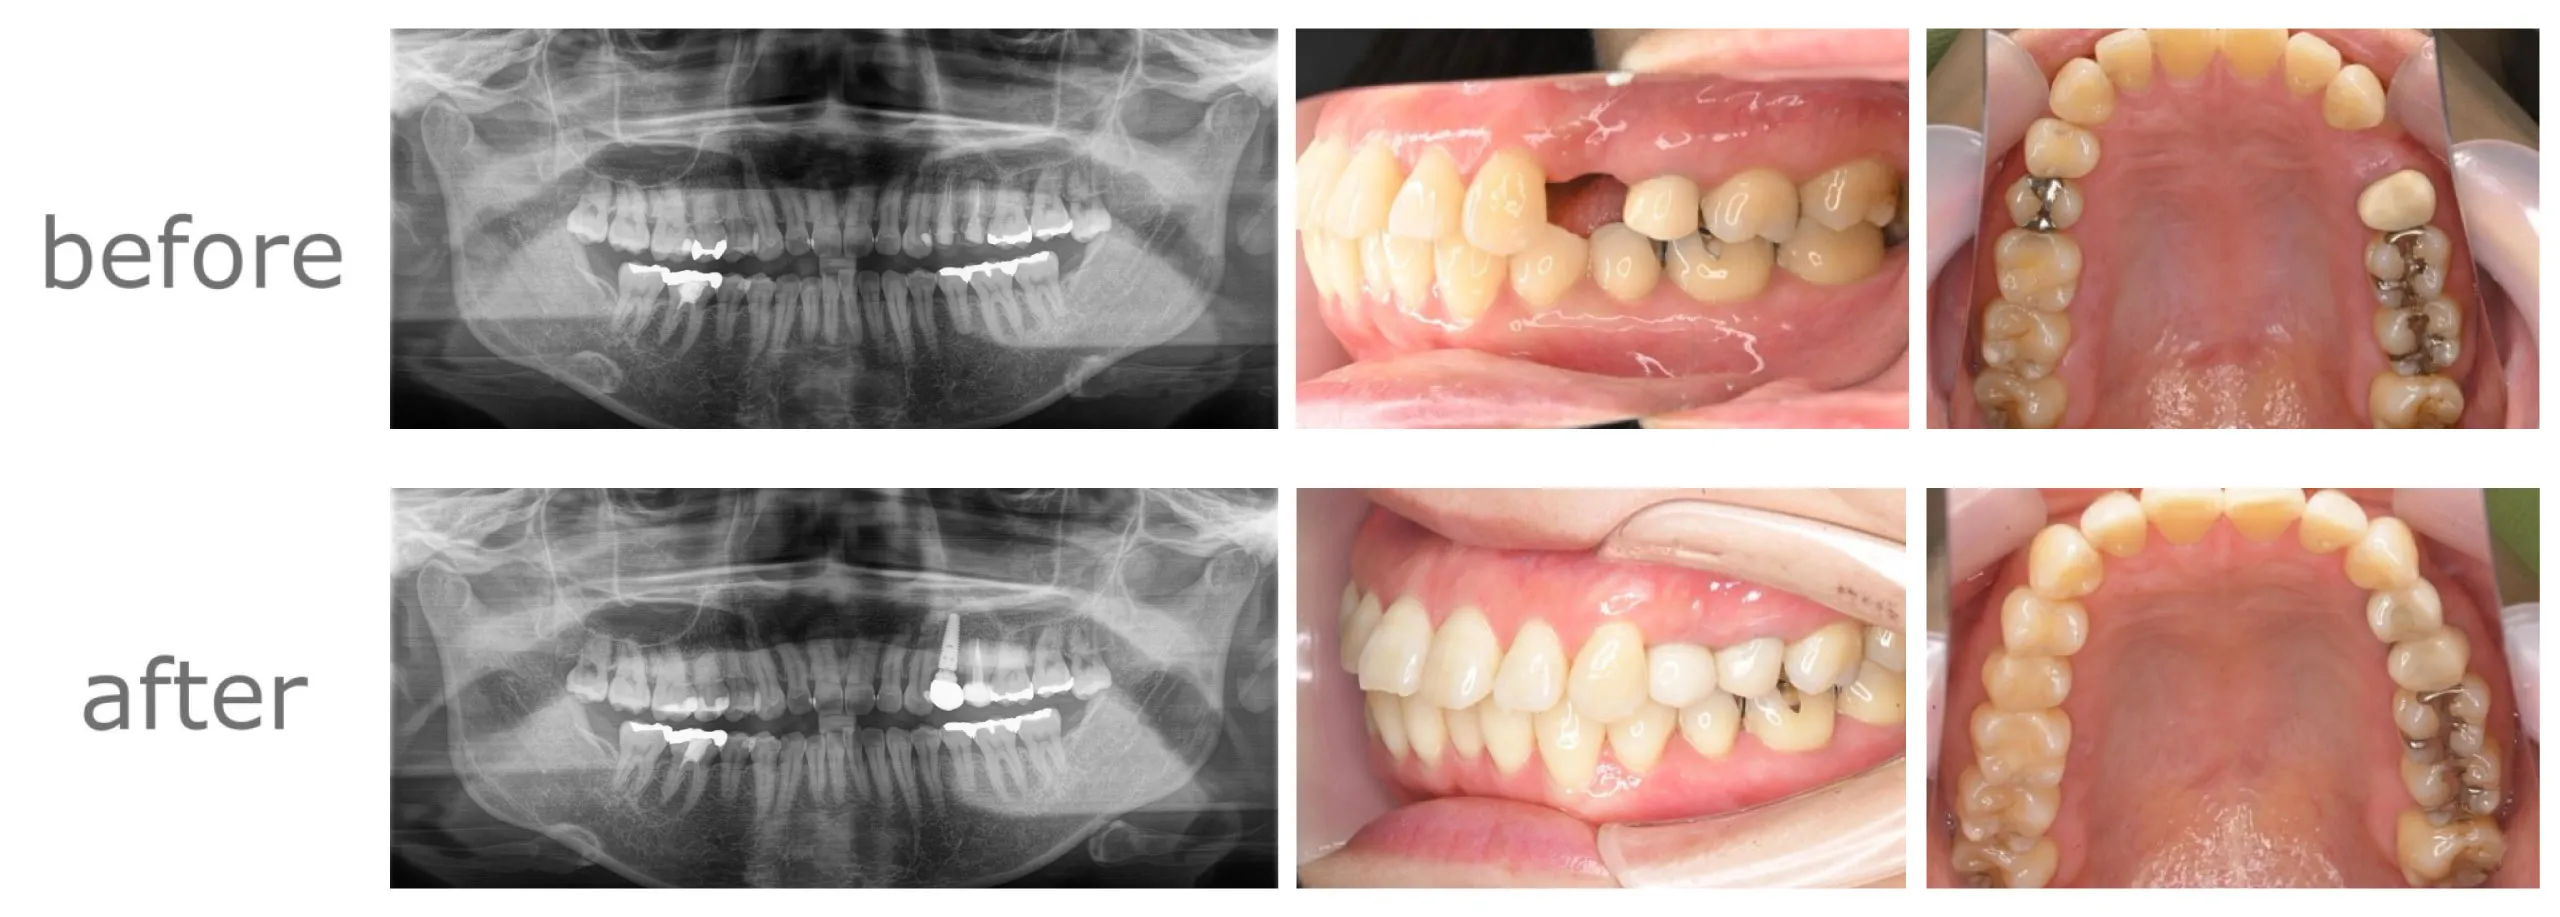

症例

【年齢・性別】

40代・女性

【主訴】

左上4、5が5年前に根っこの治療をしたが、その後左上4が2回腫れて痛い。

【期間】

8ヶ月

【通院回数】

9回

【費用】

660,000円